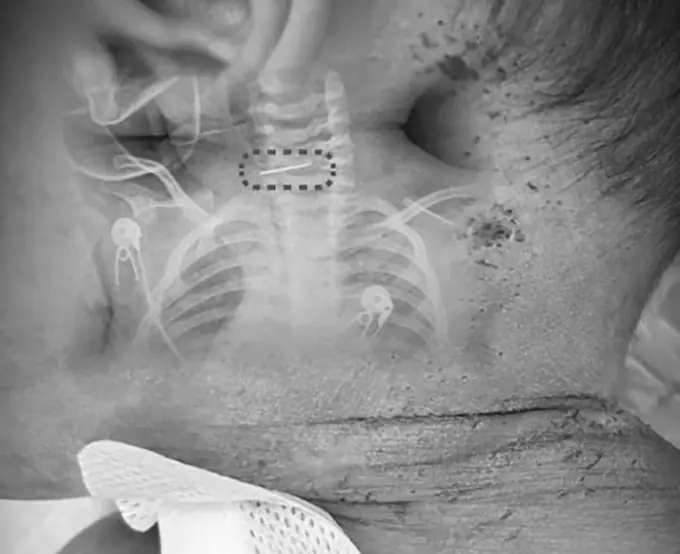

De acordo com reportagem publicada pelo South China Morning Post, um exame de raio-X revelou que uma das agulhas havia se quebrado e ficado alojada na coluna cervical da criança, o que estava relacionado ao estado clínico que motivou o atendimento de emergência.

A equipe médica realizou uma cirurgia para retirada do objeto. O procedimento foi considerado de risco, mas foi concluído de forma satisfatória. Três dias após a intervenção, o quadro de saúde do bebê foi estabilizado.